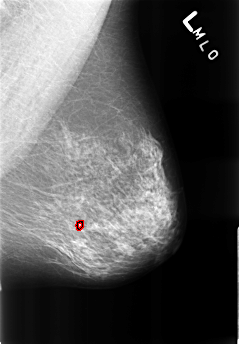

B_3220_1.LEFT_MLO

LEFT_MLO LINES 4464 PIXELS_PER_LINE 3104 BITS_PER_PIXEL 12 RESOLUTION 50 OVERLAY

FILE: B_3220_1.LEFT_MLO.OVERLAY

TOTAL_ABNORMALITIES 1

ABNORMALITY 1

LESION_TYPE CALCIFICATION TYPE COARSE-ROUND_AND_REGULAR DISTRIBUTION N/A

ASSESSMENT 2

SUBTLETY 5

PATHOLOGY BENIGN_WITHOUT_CALLBACK

TOTAL_OUTLINES 1

BOUNDARY